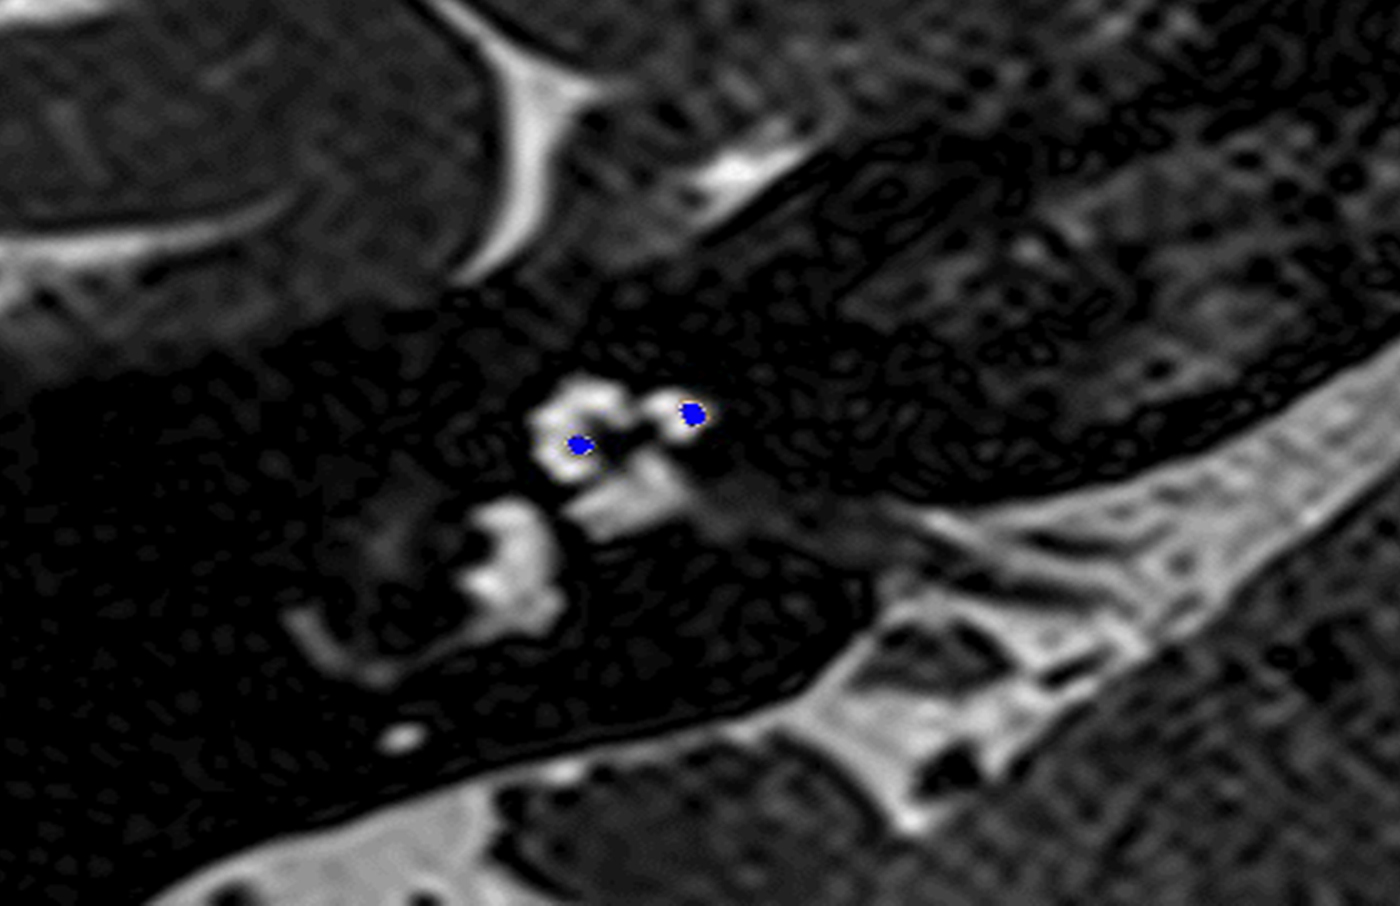

In these 19 cases, co-registration of the pre-operative MRI and post-operative cone-beam CT was performed, as described elsewhere.Reference Dragovic, Stringer, Campbell, Shaul, O'Leary and Briggs8 In short, the cone-beam CT and MRI scans were imported into the image analysis program Amira™ for semi-automatic registration. Three reference points on each image set were marked in three dimensions to allow automatic multipoint registration. The final registration was performed freehand, to ensure that the cochlea, vestibule and semicircular canals were aligned, with researcher satisfaction determining the final endpoint. This allowed accurate assessment of electrode position for these cases (Figures 1–3).

Fig. 3. Co-registered image of pre-operative magnetic resonance imaging and post-operative cone-beam computed tomography scans showing the electrode translocated from scala tympani to scala vestibuli.